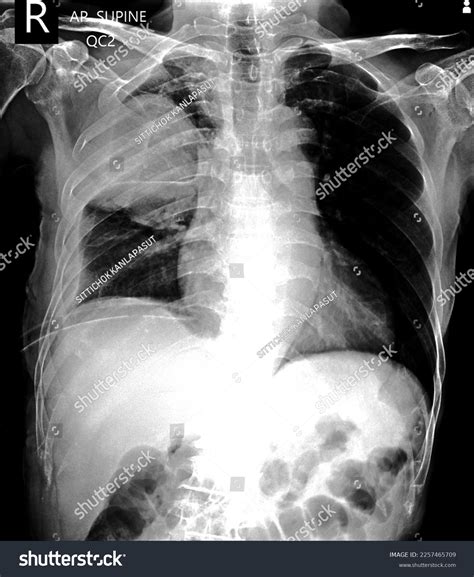

• Chest X-ray: This is often the first-line imaging study used to diagnose pneumothorax. It can detect the presence of air in the pleural space and assess the size of the pneumothorax.

In addition to imaging studies, clinical symptoms and physical examination findings play a crucial role in diagnosing pneumothorax. Common symptoms include: